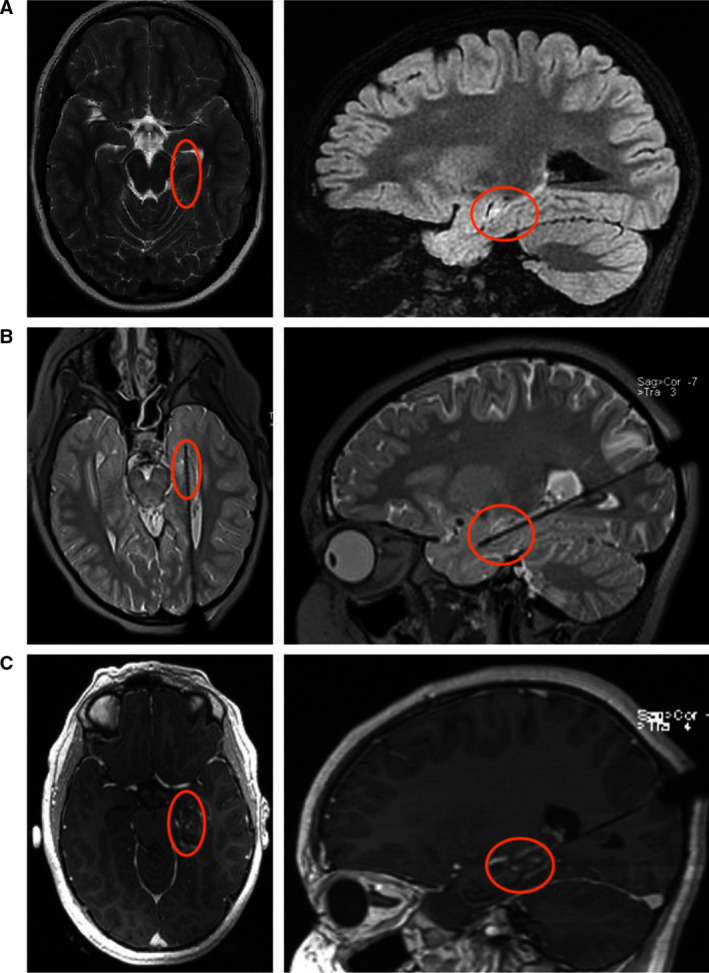

激光间质热疗(LITT)过程:(A)描绘左侧海马硬化的轴向T2加权和矢状面衰减倒置恢复(FLAIR)磁共振成像(MRI)切片。(B)通过枕骨入路沿海马长轴插入的激光探针。(C)激光消融后获得的早期T1对比增强MRI显示病变的大小。